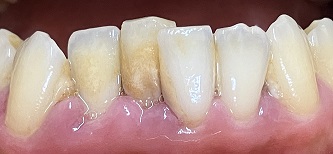

下画像1

唇側に歯石の付着 歯肉の腫れあり